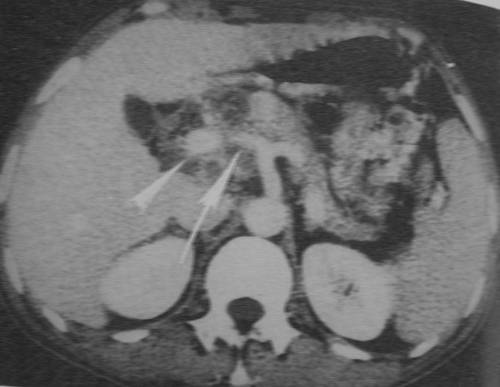

7、体格检查除发现黄疸外,可有上腹部压痛。晚期可于上腹部触及结节状、质硬之肿块。如黄疸伴有胆囊肿大,则为胰头癌的重要依据。由于胆汁淤积,常可扪及肝脏肿大。如癌肿压迫脾静脉或脾静脉血栓形成时,可扪及脾肿大。